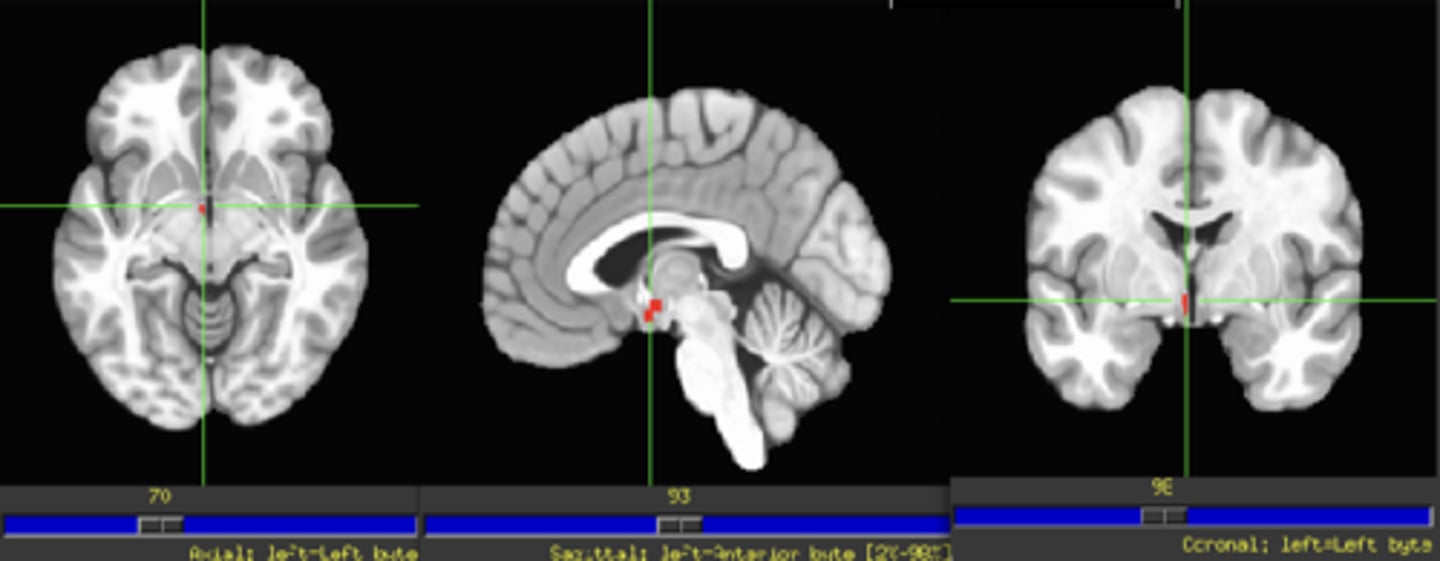

Mesocortical Pathway

VTA ←> PFC

Mesolimbic Pathway

VTA ←> NAc